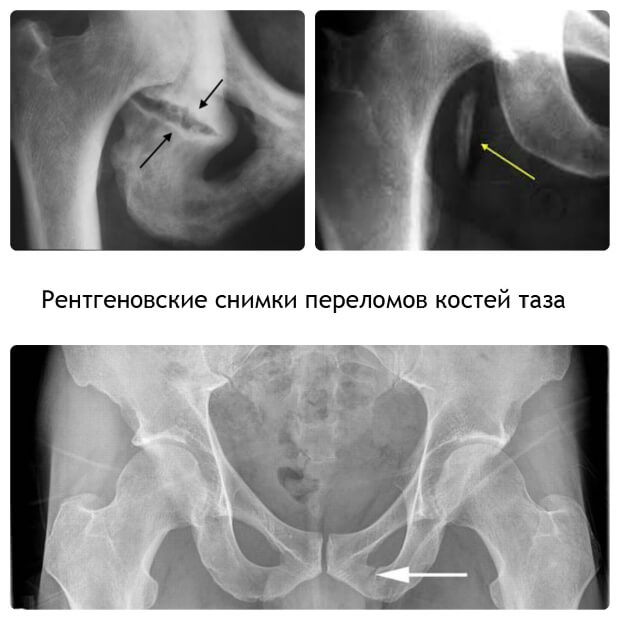

- Ретнгенография.

Врачом назначается рентгенография.

По результатам диагностики может быть назначена уретрография или цистография.

При обследовании назначается рентгенография, после осуществляется лечение, которое проходит в течение месяца.